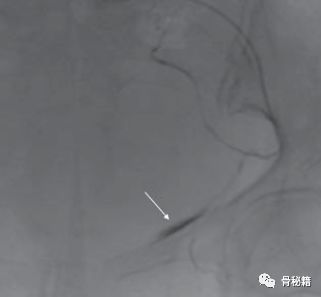

1.受伤时怀疑损伤可以做CT,腹部B超,腹腔穿刺等来进行诊断,B超的敏感性不强,CT有时可以发现耻骨附近的血肿。实在不行可以做造影。

行血管造影后确定了为死亡之冠出血,后行血管栓塞闭孔动脉后,出血停止。一周后康复出院。